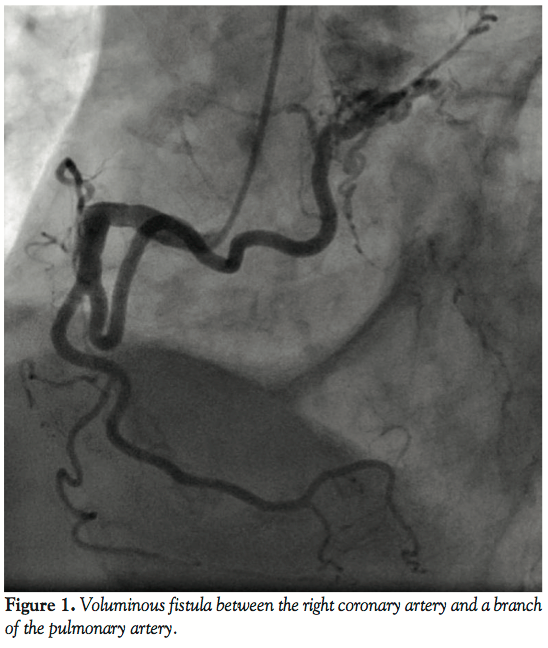

A coronary angiogram showed no signs of atherosclerotic coronary artery disease. However, it revealed a voluminous fistula between the proximal segment of the right coronary artery and a branch of the pulmonary artery. Without other plausible causes for her condition, the patient was subsequently called for percutaneous closure of the coronary fistula, which was successfully performed using 3 AZUR embolization coils (platinum coils coated with hydrocolloid gel). Figures 1-3 show the coronary fistula before, during, and after the procedure. One month later, she is asymptomatic.